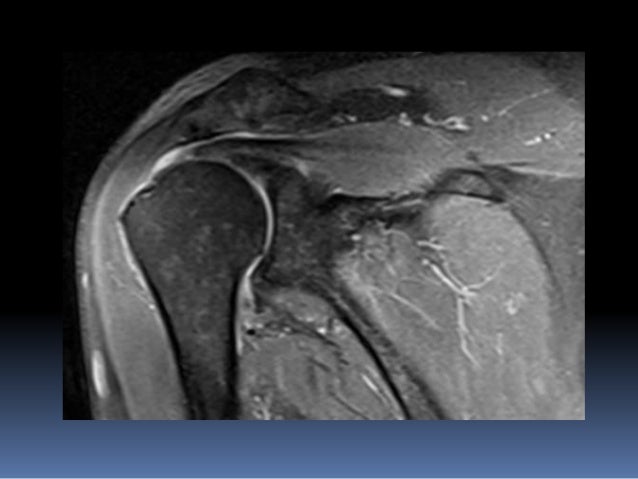

Adhesive Capsulitis (frozen Shoulder) | Image | Radiopaedia.org

shoulder adhesive frozen capsulitis radiopaedia stir tear pain case